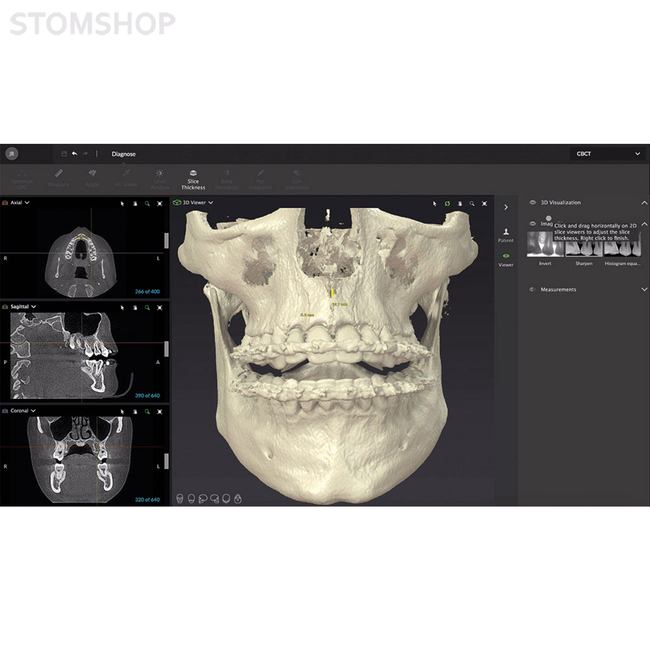

OP 3D Vision - обновляемая 3D-система для самых требовательных задач. Вне зависимости от ваших запросов, рентгенографическая система KaVo OP 3D Vision будет хорошим ответом на них. Причем совершенно неважно, как вы намерены использовать установку: для имплантологии, хирургии, эндодонтии, ВНЧС, исследования дыхательных путей или ортодонтии. Даже при наличии сложных показаний гарантируется быстрая диагностика и упрощенное планирование лечения.

Необходимое вам программное обеспечение будет установлено в OP 3-D Vision во время эксплуатационного запуска. В перечне предустановленного ПО есть поддержка трехмерной рентгенографии, хирургические шаблоны для планирования имплантатов и имплантационной хирургии, другие варианты применения по выбору.

Ваша рентгенографическая система KaVo OP 3-D Vision готова для будущей эксплуатации: вы можете заказать DTX Studio, новую программную платформу, разработанную в виде целостной системы организации технологических процессов. DTX Studio постоянно оптимизируется и охватывает все области современной стоматологии и дентальной технологии в будущем. DTX Studio совместимо с операционными системами Mac и Windows. Оно будет объединять как уже существующие, так и проектируемые устройства многочисленных брендов, а также современные возможности программного обеспечения в объединенный рабочий процесс.